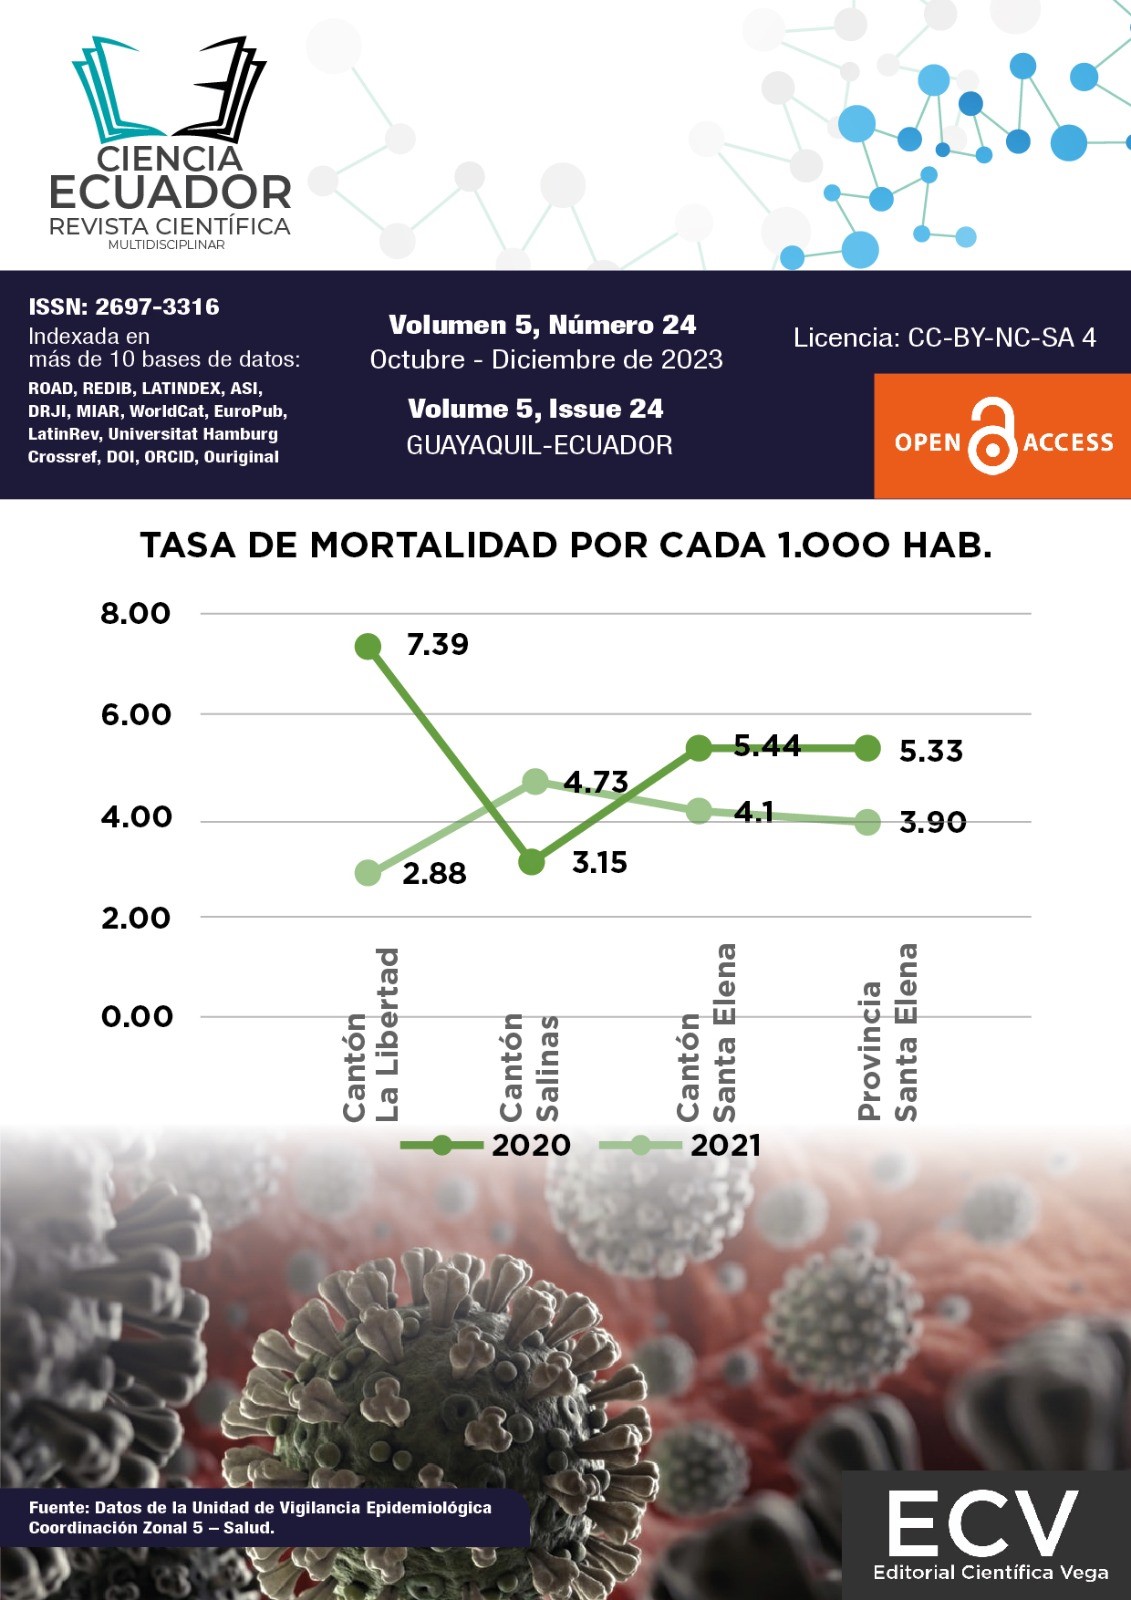

Los últimos apuntes de COVID-19, analgesia multimodal, ictus isquémico, entre otros

Vol. 5 Núm. 24 (2023) -